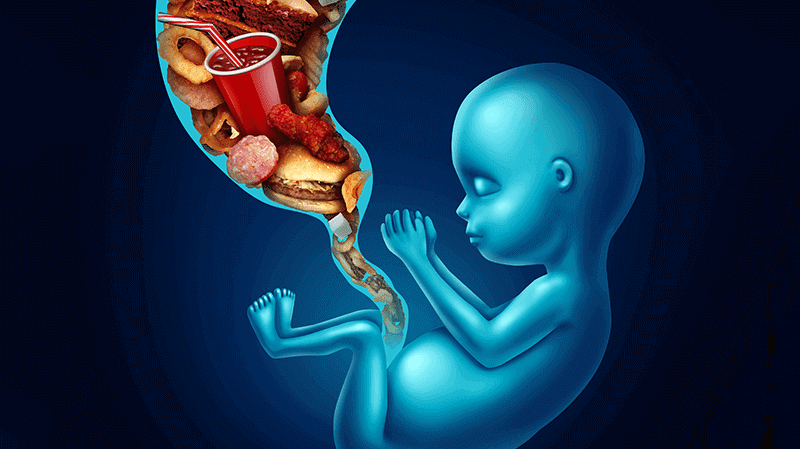

Dr. Manisha Chaudhary is the top laparoscopic gynaecologist and infertility specialist in Meerut. She is well-known for assisting many couples in becoming parents, as well as for her compassionate and informed approach to women's healthcare. Dr. Manisha Chaudhary can help you with all of your laparoscopic gynaecological and infertility requirements in Meerut. That is why she is considered the best female doctor in Meerut. Dr. Manisha Chaudhary is passionate about the most recent management protocols. She is skilled at managing high-risk pregnancies, infertility, and laparoscopic surgery, including normal delivery.Over the last 30 years, we've built a reputation for delivering one-on-one care to Meerut women.-Best Gynecologist in Meerut